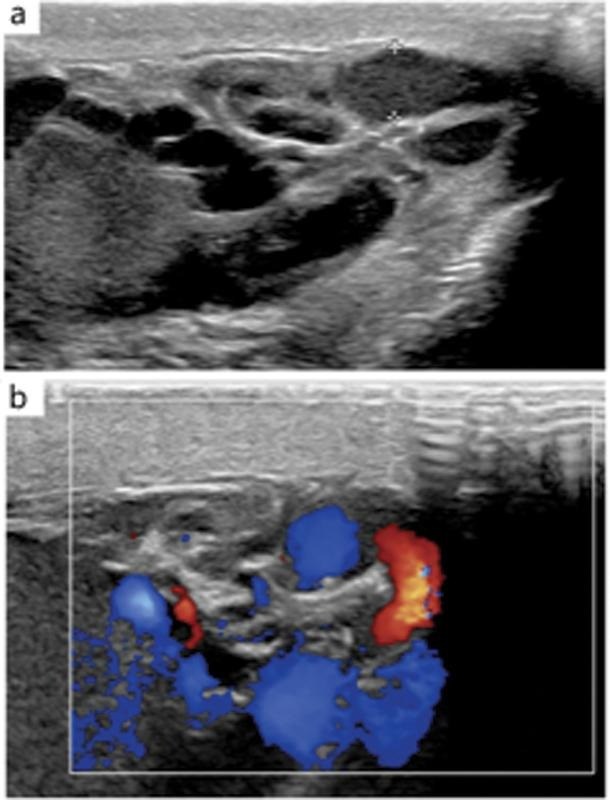

Gambar 1. USG evaluasi dari pasien varikokel kiri

Peralatan: Pemeriksaan harus dilakukan menggunakan transduser linear frekuensi tinggi (biasanya >7.5 MHz). Frekuensi tinggi memberikan resolusi spasial yang superior, yang penting untuk memvisualisasikan struktur vena kecil di dalam pleksus pampiniformis dengan jelas.

Pada B-mode atau grayscale ultrasound, varikokel tampak sebagai kumpulan struktur tubular (seperti tabung), anekoik (hitam), dan serpiginosa (berkelok-kelok) di dekat aspek superior dan lateral testis. Parameter kuantitatif utama yang dinilai adalah diameter vena terbesar dalam pleksus pampiniformis. Meskipun terdapat beberapa variasi dalam literatur, ambang batas diameter yang paling umum diterima dan direkomendasikan untuk mendiagnosis varikokel adalah ≥3 mm. Pengukuran ini idealnya dilakukan saat pasien dalam posisi berdiri dan melakukan manuver Valsalva untuk memastikan dilatasi maksimal.

Jika penilaian B-mode mengevaluasi aspek struktural (dilatasi), maka Doppler ultrasound mengevaluasi aspek fungsional (hemodinamik). Deteksi dan kuantifikasi aliran darah retrograde (refluks) adalah pilar kedua dalam diagnosis varikokel.

Color Doppler memberikan visualisasi langsung dari aliran darah. Saat pasien melakukan manuver Valsalva, adanya refluks akan terlihat sebagai perubahan warna yang tiba-tiba pada pembuluh darah (misalnya, aliran yang tadinya berwarna biru menjauhi transduser, berubah menjadi merah menuju transduser), yang menandakan pembalikan arah aliran.